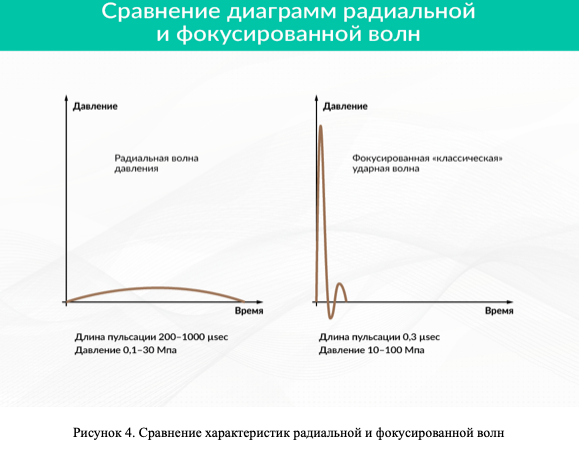

Наряду с «классическими» ударными волнами, о которых идет речь выше, выделяют еще радиальные ударные волны. Они имеют отношение к так называемым расфокусированным волнам давления, которые расходятся из источника широким потоком во все стороны и чем-то напоминают воду, льющуюся из душа. Радиальные ударные волны не имеют фокусного пятна, где концентрируется энергия. Их начали использовать в медицине в 1999 г.

Характеристики радиальной волны давления сильно отличаются от «классических» ударных волн, в том числе и по эффектам, оказываемым на организм. Для них характерен:

- растянутый во времени пологий фронт — давление нарастает по краю в области повышенного давления в миллисекундном диапазоне (то есть нарастает более длительно);

- небольшие, относительно «классической» ударной волны, величины давления перед и за фронтом, и, соответственно, высокие потери энергии в первых 5 мм тканей тела при вхождении;

- равномерное распределение во все стороны от источника ударной волны;

- малая плотность потока энергии на единицу площади — в десятки раз меньшая, чем у фокусированной волны (рисунок 4).

Наряду с «классическими» ударными волнами, о которых идет речь выше, выделяют еще радиальные ударные волны. В акустике они имеют отношение к так называемым расфокусированным волнам давления, которые расходятся из источника широким потоком во все стороны и чем-то напоминают воду, льющуюся из душа. Радиальные ударные волны не имеют фокусного пятна, где концентрируется энергия. Их начали использовать в медицине в 1999 г.

Характеристики радиальной волны давления сильно отличаются от «классических» ударных волн, в том числе и по эффектам, оказываемым на организм. Для них характерен:

- растянутый во времени пологий фронт — давление в области повышенного давления нарастает в миллисекундном диапазоне (то есть более длительно, чем у «классических» ударных волн);

- небольшие, относительно «классической» ударной волны, величины давления перед и за фронтом, и, соответственно, высокие потери энергии в первых 5 мм тканей тела при вхождении;

- равномерное распределение во все стороны от источника ударной волны;

- малая плотность потока энергии на единицу площади — в десятки раз меньшая, чем у фокусированной волны (Рисунок 4).